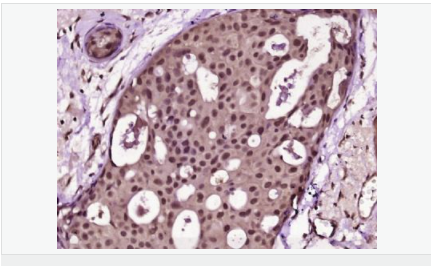

| 產品應用 | ELISA=1:5000-10000 IHC-P=1:100-500 IHC-F=1:100-500 Flow-Cyt=1μg/Test (石蠟切片需做抗原修復) not yet tested in other applications. optimal dilutions/concentrations should be determined by the end user. |

| 產品介紹 | Proliferation Marker Ki67 antigen is the prototypic cell cycle related nuclear protein, expressed by proliferating cells in all phases of the active cell cycle (G1, S, G2 and M phase). It is absent in resting (G0) cells. Ki67 antibodies are useful in establishing the cell growing fraction in neoplasms (immunohistochemically quantified by determining the number of Ki67 positive cells among the total number of resting cells = Ki67 index). In neoplastic tissues the prognostic value is comparable to the tritiated thymidine labelling index. The correlation between low Ki67 index and histologically low grade tumours is strong. Ki67 is routinely used as a neuronal marker of cell cycling and proliferation. Function: Thought to be required for maintaining cell proliferation. Subcellular Location: Nucleus. Chromosome. Predominantly localized in the G1 phase in the perinucleolar region, in the later phases it is also detected throughout the nuclear interior, being predominantly localized in the nuclear matrix. In mitosis, it is present on all chromosomes. Similarity: Contains 1 FHA domain. SWISS: P46013 Gene ID: 4288 Database links: Entrez Gene: 4288 Human Entrez Gene: 17345 Mouse Omim: 176741 Human SwissProt: P46013 Human SwissProt: Q91VE6 Mouse Unigene: 689823 Human Unigene: 80976 Human Unigene: 4078 Mouse Unigene: 233802 Rat Important Note: This product as supplied is intended for research use only, not for use in human, therapeutic or diagnostic applications. 細胞增殖標志物(Proliferation Marker) Ki67與PCNA一樣,為細胞增殖的一種標記,在細胞凋亡中S、G2 、M期均有表達,G0期缺如。 Ki-67增殖指數高低與許多腫瘤的分化程度、浸潤、轉移以及預后密切相關,因此被廣泛作為各種惡性腫瘤的必檢項目之一。 |